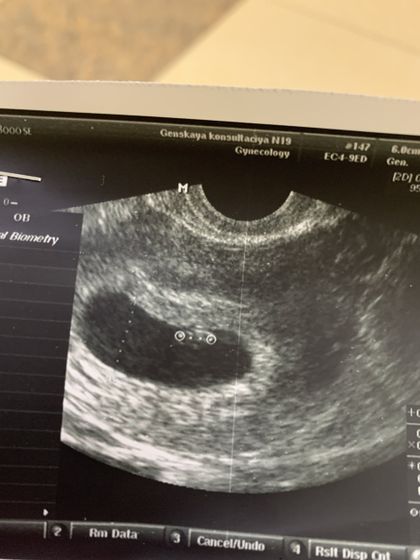

Девочки, на узи эмбриончик, ктр 7,3 мм. А желточный мешочек есть? Не вижу его. Врач ничего не сказала, очень рассеянная. Сказала все в порядке

Его может именно на этом снимке и не быть видно. А так, если есть эмбрион, то и ЖМ соответственно тоже